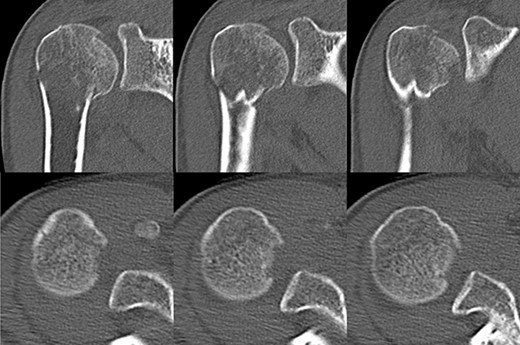

A 39-year-old man was transported via ambulance after being hit by a car. The radiographs revealed a one-part proximal humeral fracture with displacement at the surgical neck (Fig. 1). However, computed tomography (CT) revealed humeral head impression fracture and lesser tuberosity fracture in addition to a surgical neck fracture (Fig. 2). In addition, 3D-CT revealed that the collapse occupied approximately 20% of the articular surface with no glenoid defect (Fig. 3). Therefore, we first performed arthroscopic-assisted reduction and internal fixation of the humeral head impression fracture, followed by open reduction and internal fixation (ORIF) of the proximal humeral fracture.

Original CT scan showing impression fracture and surgical neck fracture.